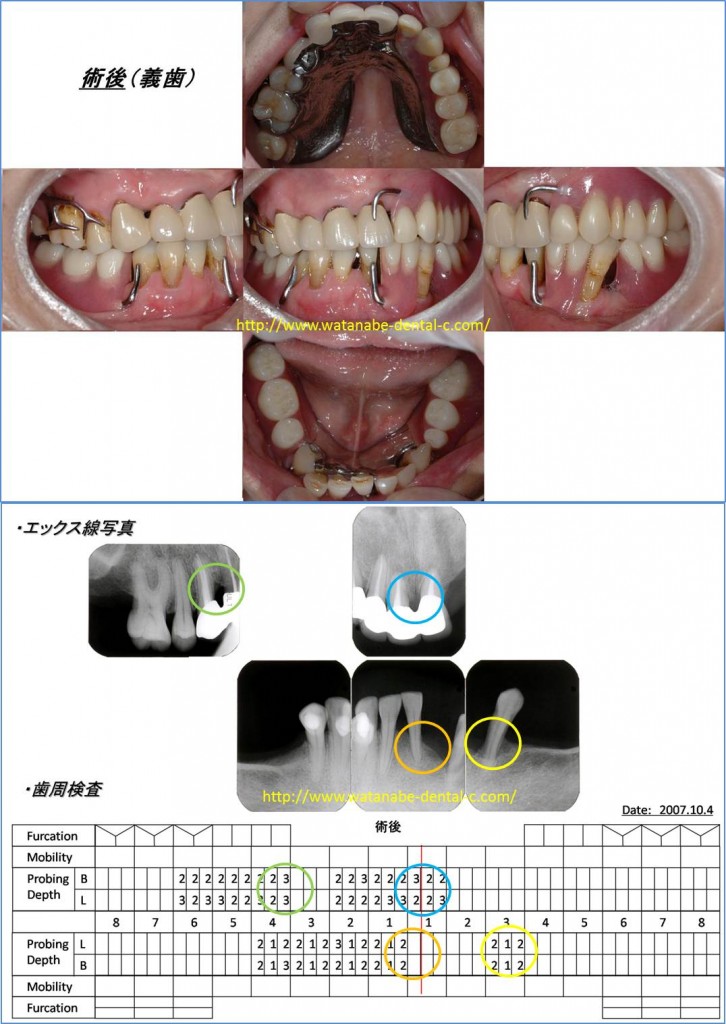

53歳女性、下の歯の動揺が気になり来院されました。下の入れ歯は気持ち悪くて入れられないとのことで、上の入れ歯だけをを装着されていました。全体的に歯肉が腫れて自然に膿が出ている状況です。エックス線所見では、○印の部分の骨吸収像、深い歯周ポケットが認められます。

そこで、「治療計画」を立案します。オレンジの○印の歯は、根の先まで骨吸収があったため抜歯の計画とし、ブラッシング指導(歯間ブラシ、歯ブラシ)、スケーリング・ルートプレーニングを行うこととしました。歯周基本治療で重要なのは、炎症性因子のコントロール(細菌を減らすこと)と歯にかかる異常な力を取り除くこと(噛み合わせの調整)が重要となります。この症例の場合、炎症を抑えることも重要ですが、奥歯に噛み合わせがないため(入れ歯を装着していないため)前歯に負担がかかります。ですから、ブラッシング指導と同時に入れ歯(プラスチックの保険の入れ歯)を製作する計画としました。

その後、再評価(歯周病の再検査)を行い、青の○印と緑の○印部分に歯肉剥離掻爬術を行いました。

術後の写真を示します。歯周外科処置後に前歯の被せものをいれて、金属床の入れ歯を装着しました。エックス線でも改善が認められ、歯周ポケットも3mm以下に改善されています。炎症のコントロールとともに、入れ歯による噛み合わせを確立し前歯の負担を軽減したことが成功につながりました。歯周病治療を成功させるには、噛み合わせも重要なのです。